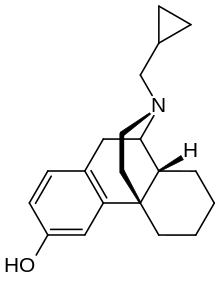

The pharmacodynamic response to an opioid depends upon the receptor to which it binds, its affinity for that receptor, and whether the opioid is an agonist or an antagonist. For example, the supraspinal analgesic properties of the opioid agonist morphine are mediated by activation of the μ1 receptor; respiratory depression and physical dependence by the μ2 receptor; and sedation and spinal analgesia by the κ receptor. Each group of opioid receptors elicits a distinct set of neurological responses, with the receptor subtypes (such as μ1 and μ2 for example) providing even more [measurably] specific responses. Unique to each opioid is its distinct binding affinity to the various classes of opioid receptors (e.g. the μ, κ, and δ opioid receptors are activated at different magnitudes according to the specific receptor binding affinities of the opioid). For example, the opiate alkaloid morphine exhibits high-affinity binding to the μ-opioid receptor, while ketazocine exhibits high affinity to ĸ receptors. It is this combinatorial mechanism that allows for such a wide class of opioids and molecular designs to exist, each with its own unique effect profile. Their individual molecular structure is also responsible for their different duration of action, whereby metabolic breakdown (such as N-dealkylation) is responsible for opioid metabolism.

Several semi-synthetic opioids were developed in Germany in the 1910s. The first, oxymorphone, was synthesized from thebaine, an opioid alkaloid in opium poppies, in 1914.[228] Next, Martin Freund and Edmund Speyer developed oxycodone, also from thebaine, at the University of Frankfurt in 1916.[229] In 1920, hydrocodone was prepared by Carl Mannich and Helene Löwenheim, deriving it from codeine. In 1924, hydromorphone was synthesized by adding hydrogen to morphine. Etorphine was synthesized in 1960, from the oripavine in opium poppy straw. Buprenorphine was discovered in 1972.[228]